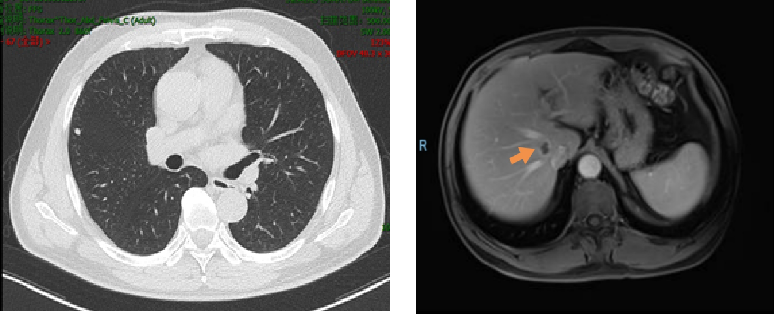

2019年3月胸部CT:右肺上叶近水平裂胸膜处有一枚结节,大小约6mm*5mm,考虑肿瘤转移;腹部MRI:肝右叶S8段新发结节,弥散受限,约16mm*12mm,考虑转移瘤可能性大。

2019.4.10于介入科行肝S8段转移瘤射频消融术。

因肝脏转移瘤靠近血管,射频消融术后复查CT认为肿瘤边缘存在强化,2019.5.27 行肝S8段转移瘤放疗,DT 40GY/5F。